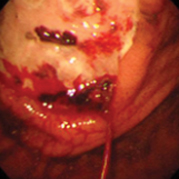

용종제거술